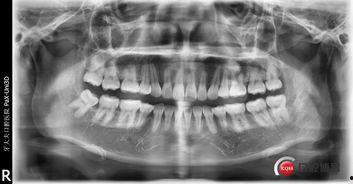

那么,细绳拔牙的原理是什么呢?其实,原理很简单。拔牙时,医生会用细绳穿过牙齿的牙缝,然后用力拉扯,使牙齿松动,最终将其拔出。这种方法看似简单,但实际上需要医生具备一定的技巧和经验。